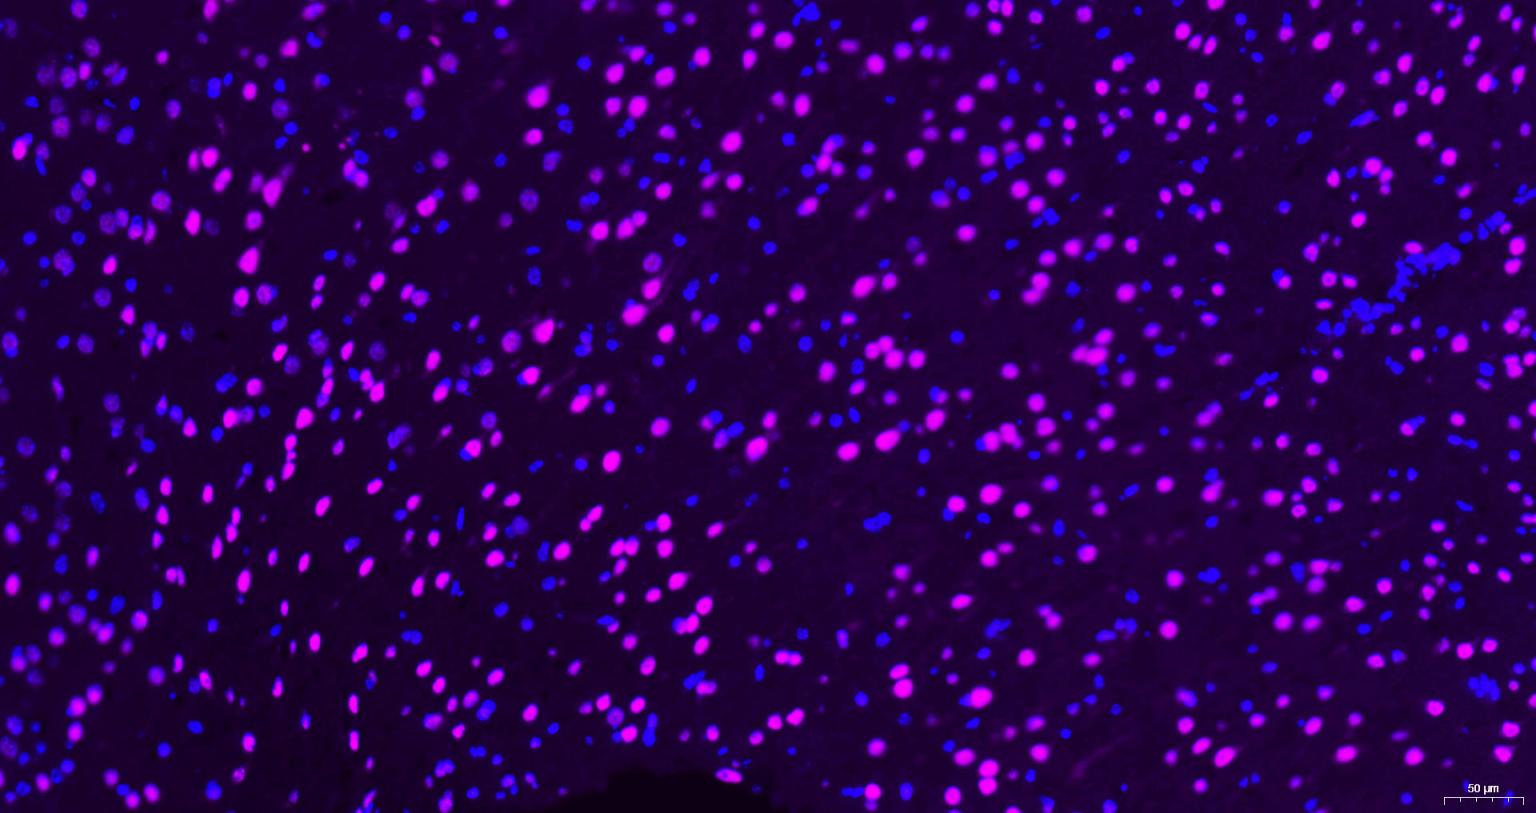

Paraformaldehyde-fixed, paraffin embedded Rat brain; Antigen retrieval by boiling in sodium citrate buffer (pH6.0) for 15 min; Antibody incubation with AKT1 Monoclonal Antibody, Unconjugated(bsm-52010R) at 1:200 overnight at 4°C, followed by a Cy5 conjugated Goat Anti-Rabbit IgG (bs-0295G-Cy5)antibody at 37°C for 90 minutes, DAPI (blue, C02-04002) was used to stain the cell nuclei.